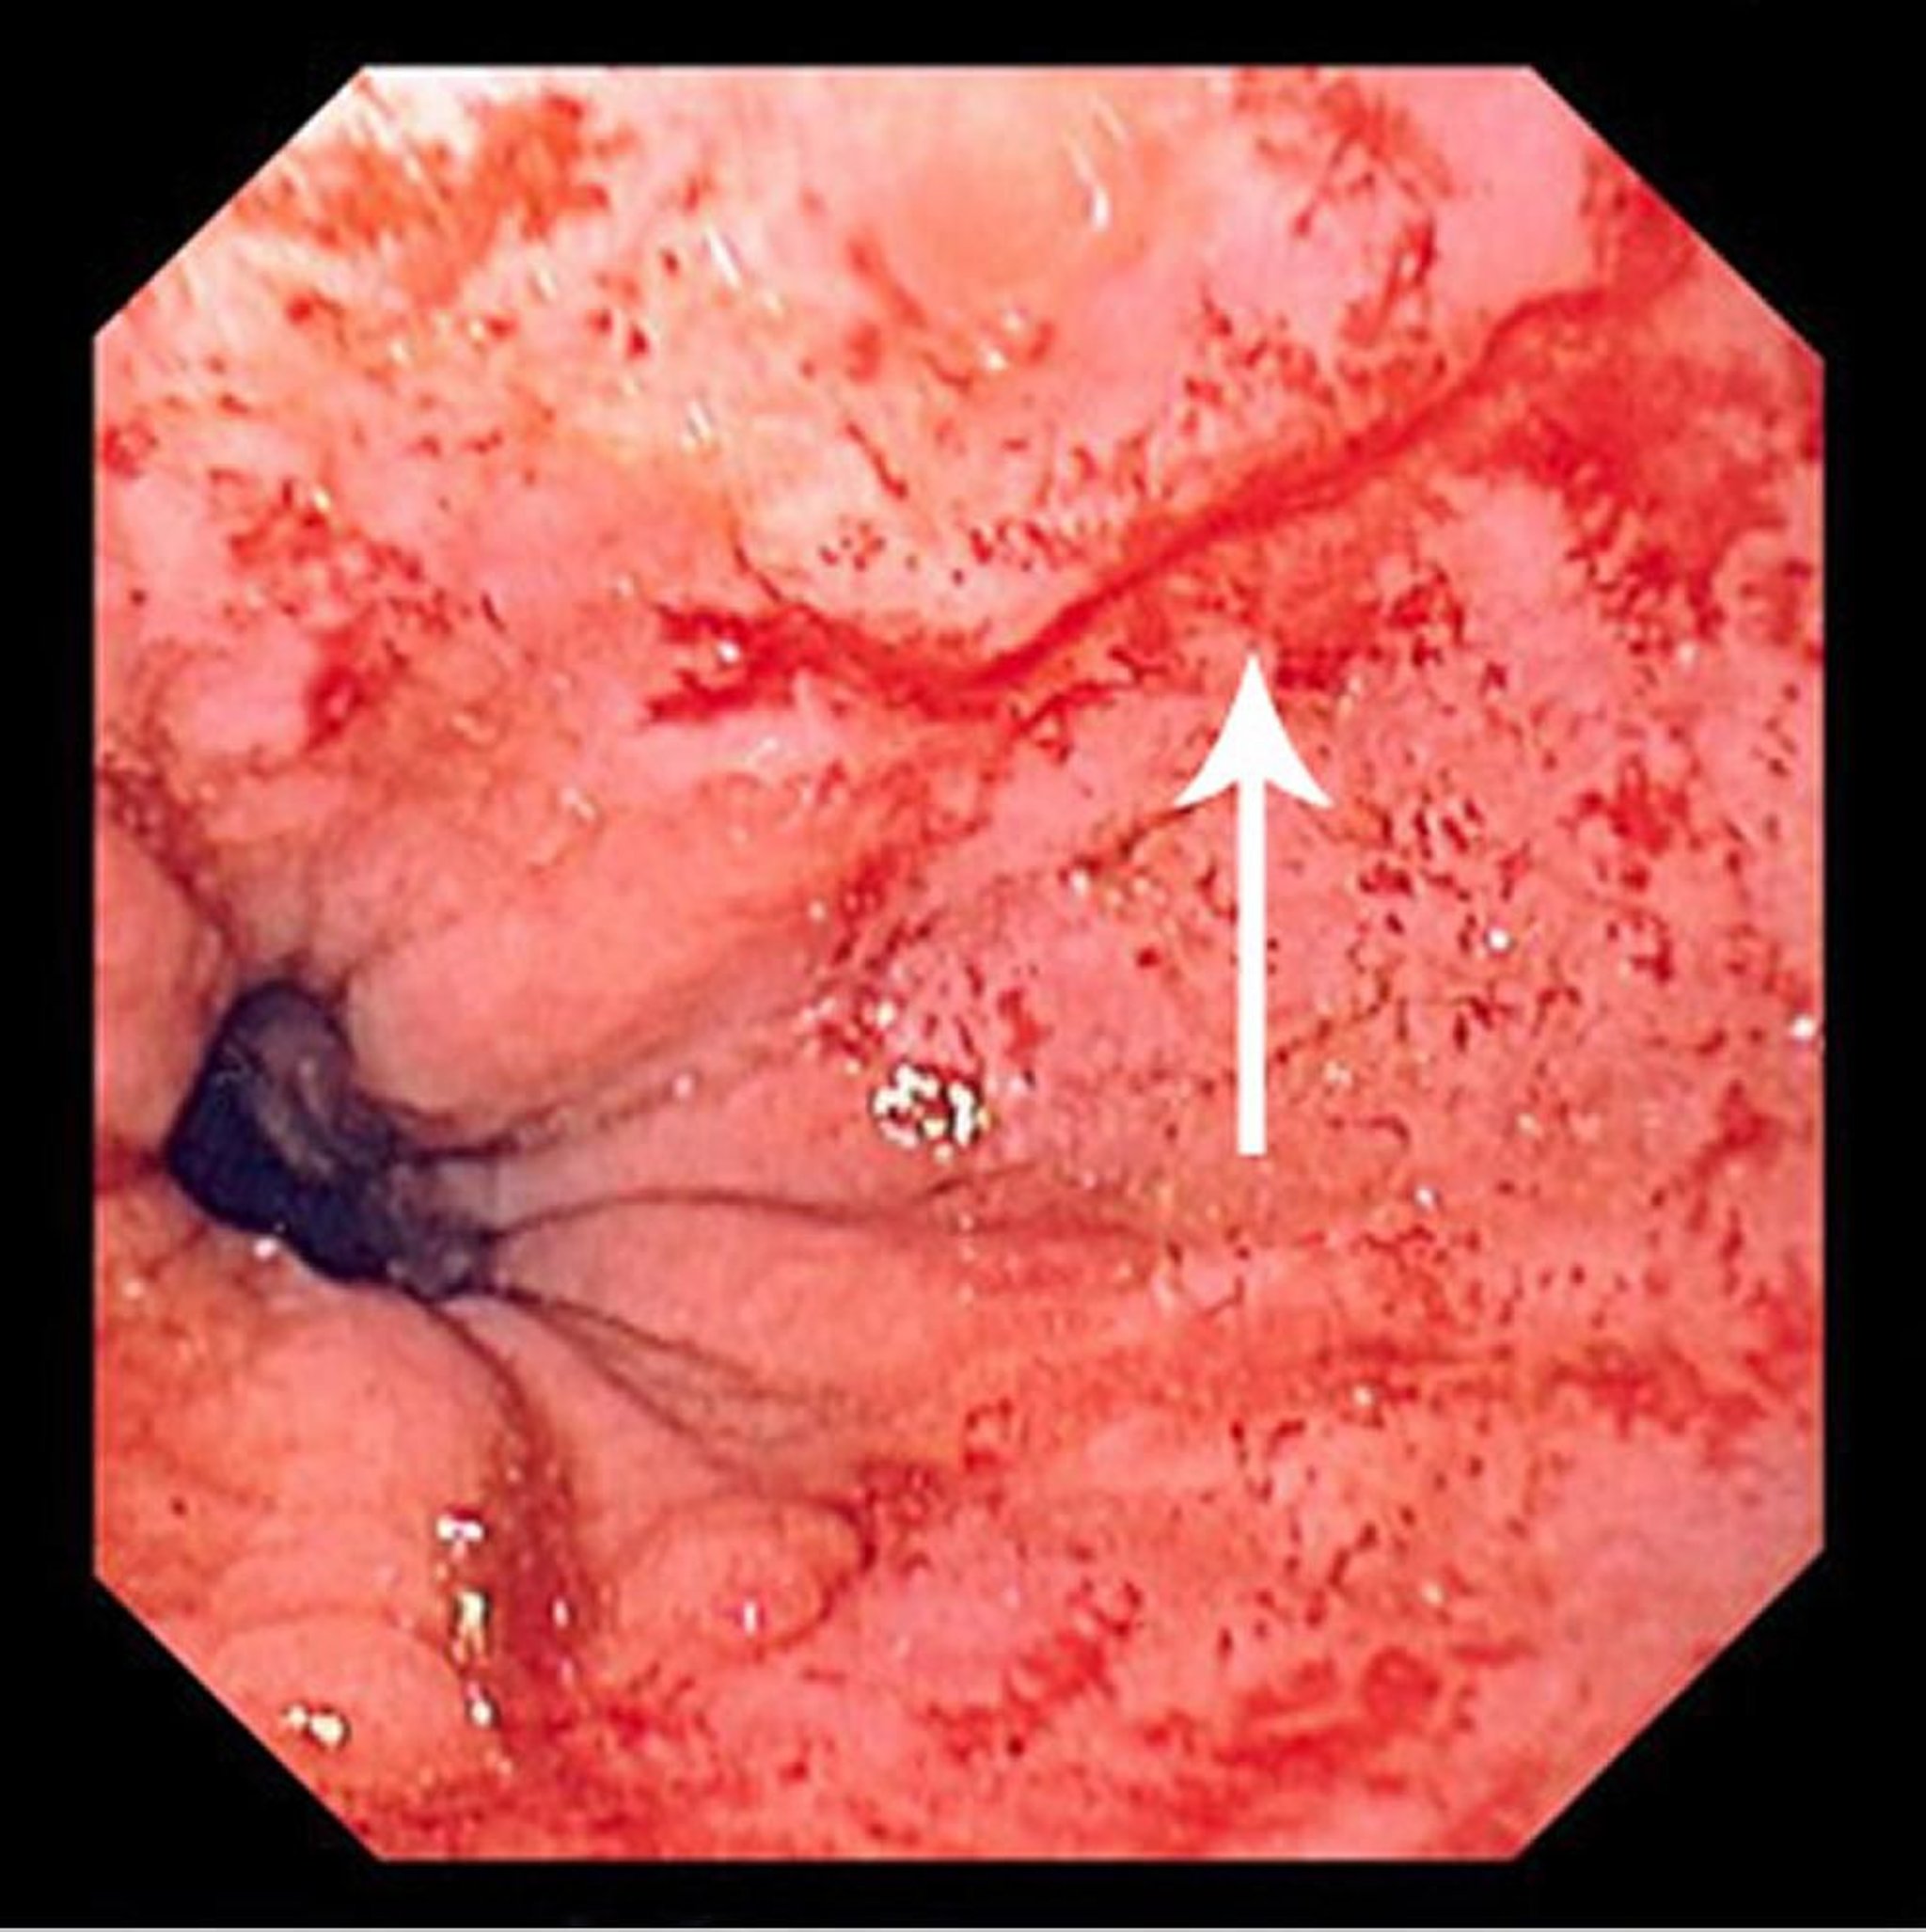

Cette photographie montre une fine déchirure de Mallory-Weiss (flèche).

Image fournie par le Dr David M. Martin.